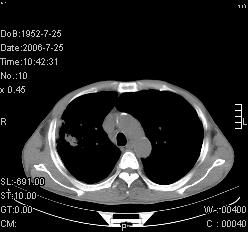

患者,男,54岁,咳嗦,咳痰20天。抗炎治疗2周。现esr76mm/h,目前患者症状明显好转,但发现两次ct片未见明显变化。两次分别做与7.25、7.31。第一次诊断右肺上叶炎症累计胸膜。大家看,从影像上内排除结核吗?

结核的可能性非常大,右上肺病变应该考虑干酪性肺炎。理由:

1.纵隔内多发淋巴结肿大。

2.esr76mm/h。

3.虽经抗炎治疗肺窗病灶有所吸收、减小,但纵隔窗病灶形态、密度、范围无明显变化。如果是单纯的大叶性肺炎,“抗炎治疗2周,目前患者症状明显好转”病灶应该基本消散了,至少也处于吸收消散期,密度变淡、范围变小。同时本病例所示其内的密度不均匀,见多发大小不一空洞样影也不符合大叶性肺炎吸收消散期表现。

病灶特点:片状 索条 结节混杂影,部分融合,密度不均,广泛累及相应胸膜.

临床治疗;二周未吸收.但症状好转.

多考虑:肺结核.